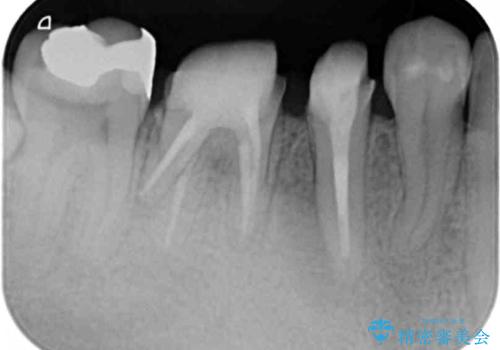

深い虫歯 セラミッククラウンの精度を高める歯周外科手術

- 歯ぐきからの排膿や出血、根尖病変の存在により他院で抜歯を提案され、歯を残す方はないかと当院に相談に見えました。

マイクロスコープを用いた根管治療を行ったのち、深い虫歯に起因する歯ぐきの腫れ・出血を改善すべく歯周外科を行いました。

歯周組織が落ち着くのを待ち、セラミッククラウンで機能・審美性を改善します。

歯内・歯周環境が整備されたことで長期的な予後の期待できるセラミック治療を行うことができました。